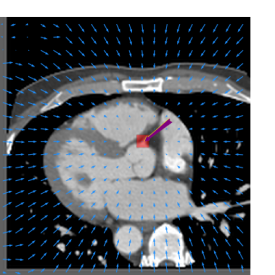

Finally, the proposed network was evaluated for the detection of five additional landmarks: the left coronary ostium, the bifurcation of the LM into the LAD and the LCx, and the origin of the left, non-coronary, and right aortic valve commissures (see Fig. 2). Fig 3 shows vector fields visualizing the predicted displacement vectors in three viewing planes in an image from the test set (for more results, see Appendix). Table 3 lists the Euclidean distance errors between the predicted landmark locations and the reference landmark locations. In addition, box-and-whiskers plots are shown in Fig 4. The best results were obtained for the origin of the right aortic valve commissure. Detection of the origin of the left aortic valve had the most narrow distribution. Outliers were seen during detection of the right ostium, the bifurcation of the LM, and the origin of the non-coronary, and the left aortic valve commissure.

Figure 3: Vector fields visualizing the predicted displacement vectors in the axial, coronal, and sagittal plane in an image from the test set where detection of the right coronary ostium was performed. The magnitudes of the vectors should point at the right ostium, but they are rescaled for visualization purposes. The red squares indicate posterior probabilities larger than 0.5, obtained by the classification network for image patches. Reference and computed landmark annotations are indicated with a yellow and purple arrow, respectively.